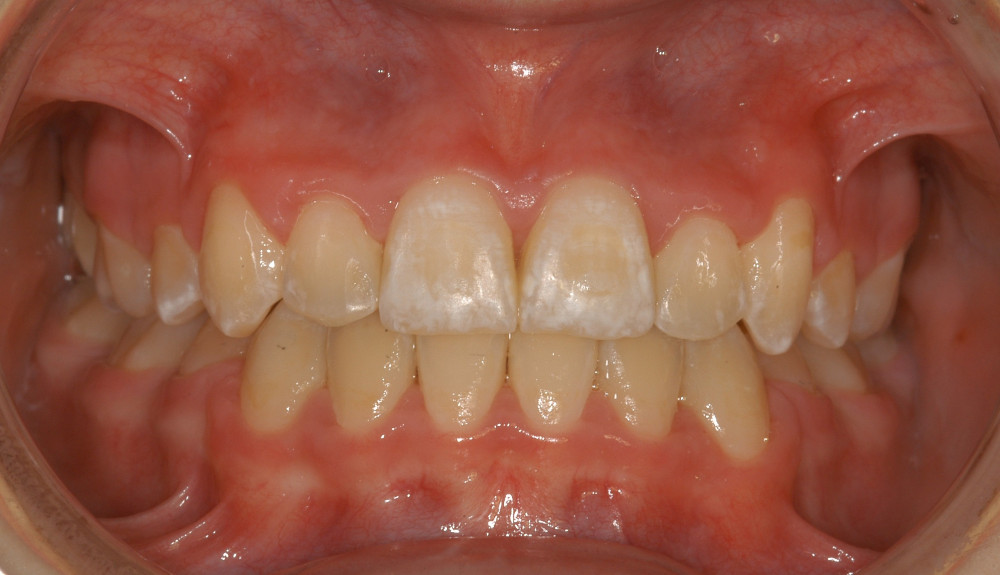

- Ein optimales und stabiles Behandlungsresultat basierend auf sehr langer Erfahrung mit dieser Therapieform.

- Die Retention (Bewahren des Resultats) nach der Behandlung machen wir mit innen geklebten, dank neuem Design gut zu reinigenden Retainer-Drähten

| Sehr schwere Kiefer-und Zahnfehlstellung Dauer ca. 2-3 Jahre, ev. mit Kieferchirurgie | Metalbrackets | ja | ja | Bild |

| ev. mit Chirurgie in Bern (Lindenhofspital) | Bild |